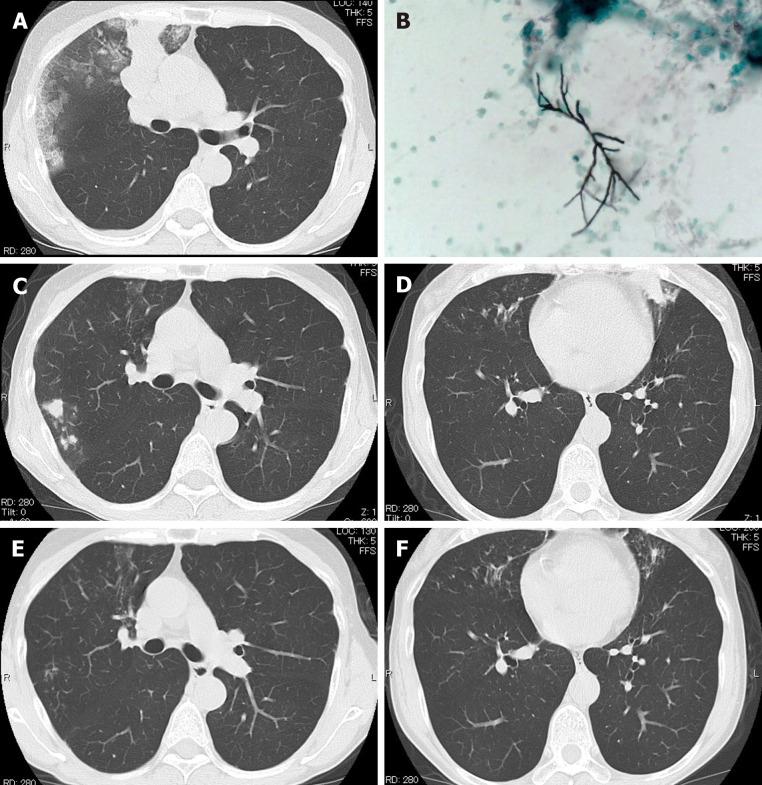

The patient was a 54-year-old woman with bronchial asthma treated with inhaled corticosteroids and a long-acting beta-2 agonist. She consulted our institution for productive cough and fever in March 2017. Chest computed tomography scan revealed mucoid impaction, and the bronchial lavage fluid culture was positive for . The diagnosis was ABPA. The patient was treated with oral glucocorticoids from April 2017 to November 2017. In January 2019, she had bronchial asthma exacerbation, and a chest computed tomography scan showed recurrent mucoid impaction. She was treated with oral glucocorticoids and itraconazole. In February 2020, during tapering of oral glucocorticoid, she had the third episode of bronchial asthma exacerbation and a mucoid impaction. The patient was treated with dupilumab in addition to oral glucocorticoid and itraconazole. The clinical response improved, and oral glucocorticoid was discontinued in June 2020.

该患者为一名54岁女性,患有支气管哮喘,接受吸入性糖皮质激素和长效β2受体激动剂治疗。2017年3月,她因咳痰和发热前来我院就诊。胸部计算机断层扫描显示黏液嵌塞,支气管灌洗液培养曲霉菌阳性。诊断为ABPA。该患者于2017年4月至2017年11月接受口服糖皮质激素治疗。2019年1月,她出现支气管哮喘加重,胸部计算机断层扫描显示复发性黏液嵌塞。她接受了口服糖皮质激素和伊曲康唑治疗。2020年2月,在口服糖皮质激素减量期间,她出现第三次支气管哮喘加重和黏液嵌塞。除口服糖皮质激素和伊曲康唑外,该患者还接受了度普利尤单抗治疗。临床反应改善,2020年6月停用口服糖皮质激素。